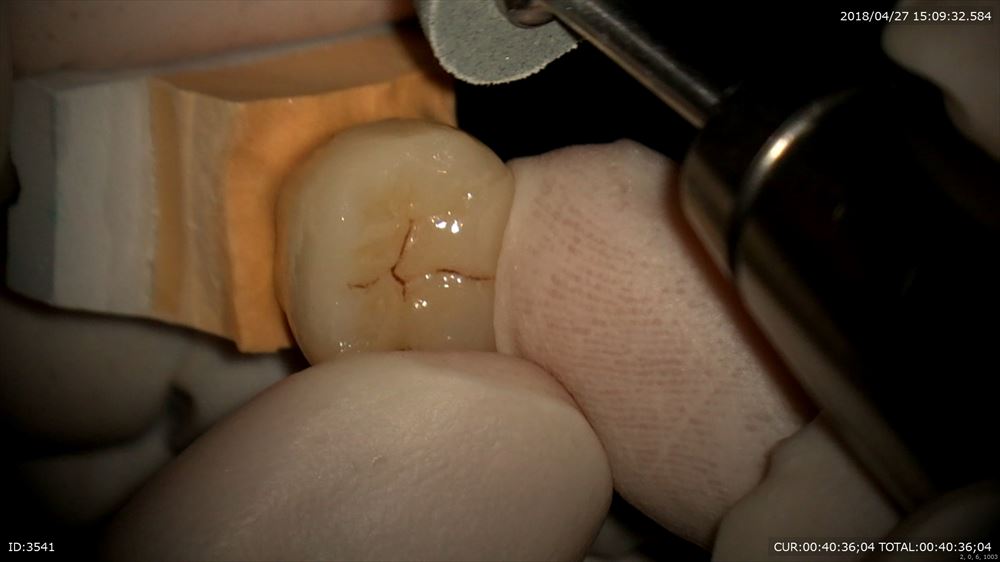

フィット

きつさの調整

吸い込まれます。ここから

吸い込まれた